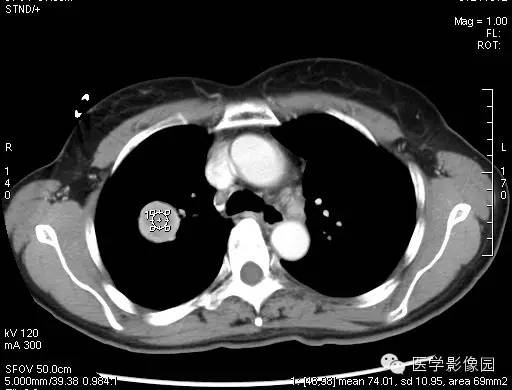

动脉期的增强在中等以上,静脉期增强在动脉期的程度上有更深程度的强化,当肿瘤边缘不清晰时,就有呈现浅分叶、胸膜凹陷、短毛刺等现象,边缘清楚、光整,多数形态规则、少数可见浅分叶,无毛刺、空洞,无卫星灶,密度均匀,偶有钙化,无胸膜凹陷征。CT增强扫描显示病灶中等以上均匀或不均匀强化,且存在延迟强化现象,对PSH具有一定的诊断价值。